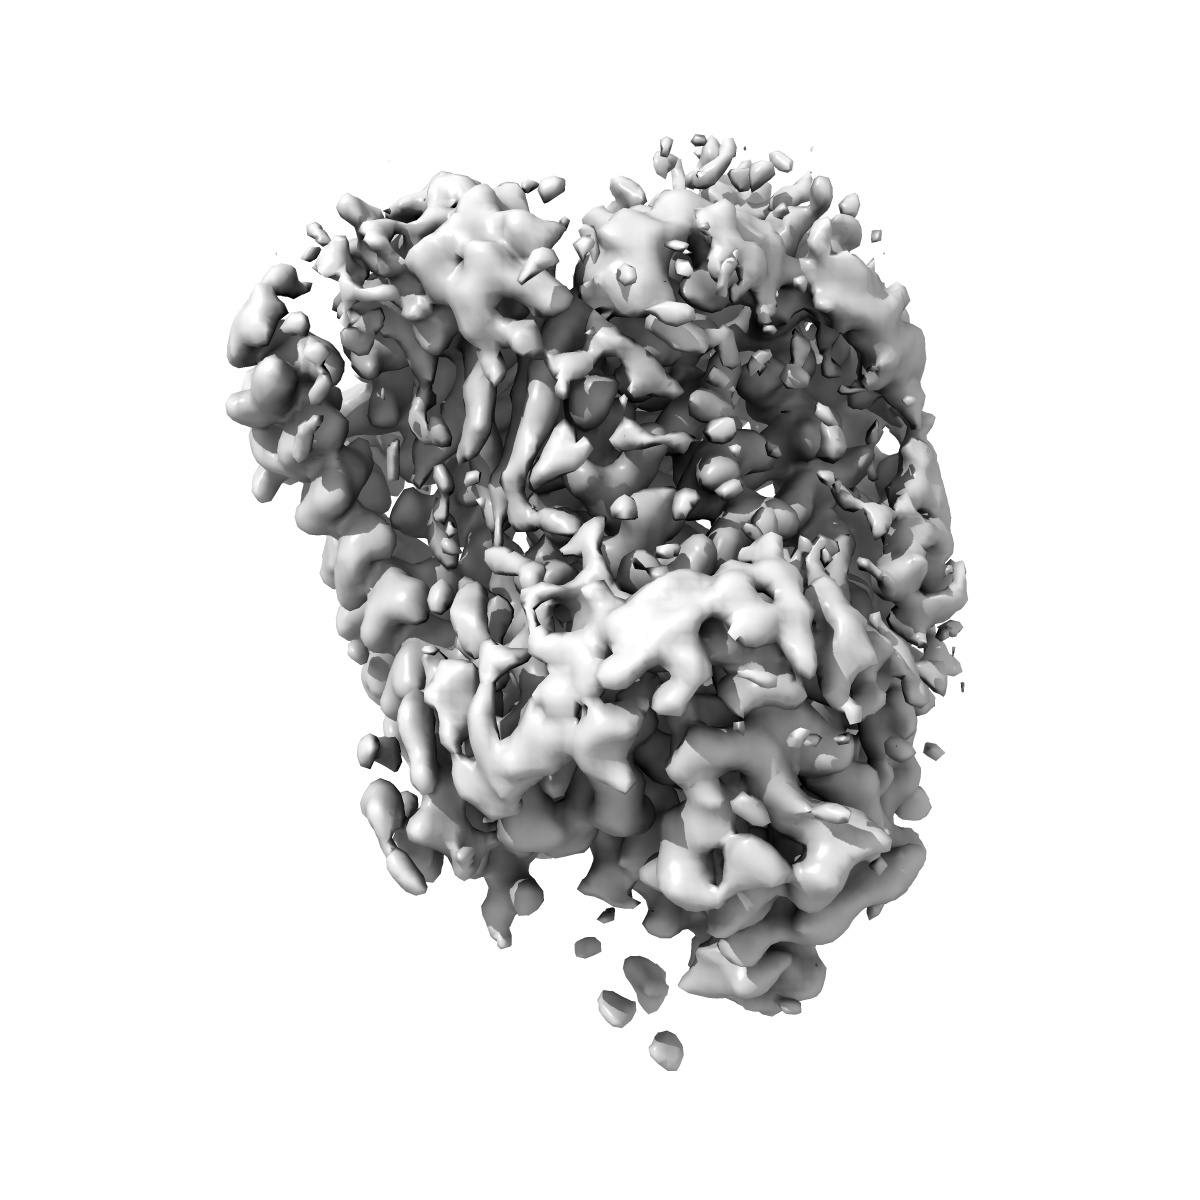

CryoEM structure of gamma2 subunit of GABA(A)R in complex with GARLH4, the TMD of Neuroligin2 from desensitised state obtained by focused refinement

Sample: CryoEM structure of gamma2 subunit of GABA(A)R in complex with GARLH4, the TMD of Neuroligin2 from desensitised state obtained by focused refinement